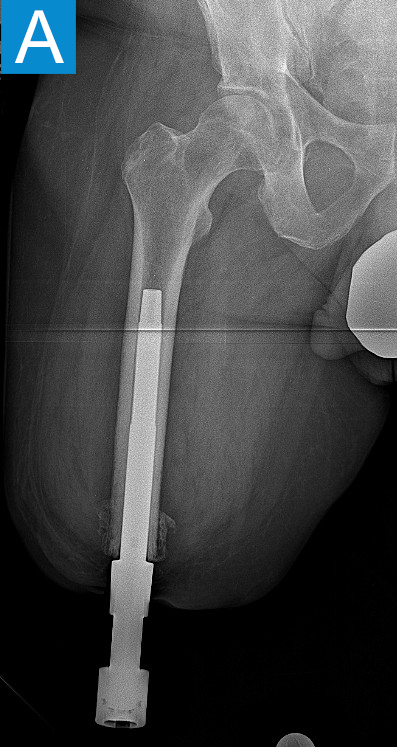

Standing radiographs showed periosteal reaction to the distal femoral isthmus, and given the chronicity of his infections the decision was made to stage the transfemoral amputation and osseointegration implant insertion (Figure 1b). During the amputation, the tibial and peroneal nerves underwent targeted muscle reinnervation to the motor branches of the medial and lateral hamstrings, respectively. Cement mixed with tobramycin and vancomycin was placed in the femoral canal, and the remaining musculature was purse stringed around the residual femur. His proximal cultures were negative, and so no further antibiotic treatment was given. Approximately 8 weeks later, the antibiotic spacer was removed and a press fit femoral osseointegration implant was placed in a percutaneous procedure (Figure 2a). Cultures of the canal remained negative.

He started progressively loading the implant at 2 weeks and received his full prosthetic leg with simple hinged knee at 6 weeks. At 3 months he no longer used assist devices and at 3.5 months his prosthesis was changed to a microprocessor-controlled knee. Shortly after receiving the new knee, he stumbled stepping over a ledge and fell, sustaining a subtrochanteric proximal femur fracture (Figure 2b). The fracture extended to the tip of the implant, which remained stable in the bone. He underwent open reduction and internal fixation of the femur fracture with a proximal locking plate (Figure 2c). He did not wear the prosthetic leg for 10 weeks, when he began gradually loading the femur. He resumed full weightbearing without assistive devices about 6 weeks later.

Figure 2. Postoperative X-rays shows (A) a femoral osseointegration implant; (B) a subtrochanteric proximal fracture; (C) the femur fracture repaired by open reduction and internal fixation with a proximal locking plate.